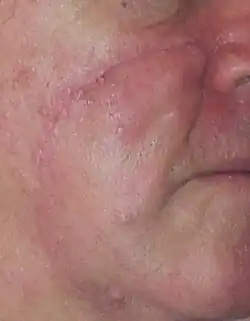

Lentigo Maligna Melanoma, Left Central Malar Cheek marked for biopsy

Lentigo Maligna Melanoma, Left Central Malar Cheek marked for biopsy